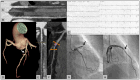

Cardiac computed tomography (CT) was introduced in the late 1990's. Since then, an increasing body of evidence on its clinical applications has rapidly emerged. From an initial emphasis on its technical efficiency and diagnostic accuracy, research around cardiac CT has now evolved towards outcomes-based studies that provide information on prognosis, safety, and cost. Thanks to the strong and compelling data generated by large, randomized control trials, the scientific societies have endorsed cardiac CT as pivotal diagnostic test for the management of appropriately selected patients with acute and chronic coronary syndrome. This consensus document endorsed by the European Association of Cardiovascular Imaging is divided into two parts and aims to provide a summary of the current evidence and to give updated indications on the appropriate use of cardiac CT in different clinical scenarios. This first part focuses on the most established applications of cardiac CT from primary prevention in asymptomatic patients, to the evaluation of patients with chronic coronary syndrome, acute chest pain, and previous coronary revascularization.

Keywords: acute chest pain; chronic coronary syndrome; coronary artery bypass graft; coronary calcium; coronary computed tomography angiography; coronary stent.